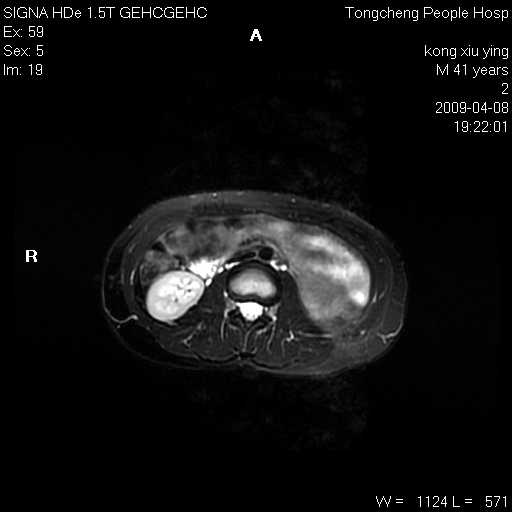

标题: CL1008:【经典】胆囊石榴籽样结石。

女,41岁。健康体检——彩超提示:胆囊显示不清。平素健康,无不适感。

腹部mr扫描及mrcp,图像如下: